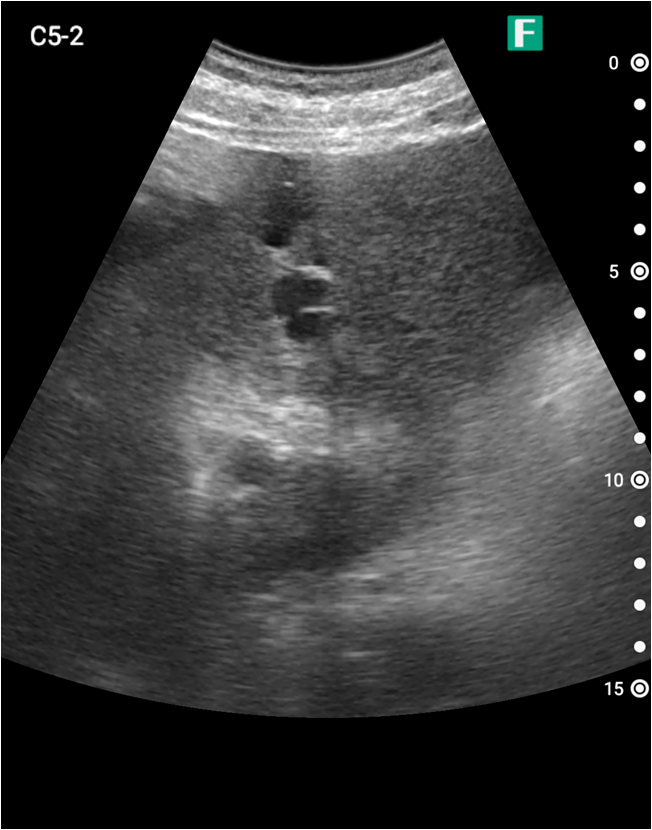

もう一つは入院患者様に対しての具体的な使用事例を紹介します。朝の回診の際にiViz airを使用し、例えば腹水のある患者様を診た際は、「今日は水の量が少なく、そこまでお腹は張ってないですね」、「今日はここに水が溜まっているんですけど、昨日より少ないですよ」など、日々の状態を患者様ご本人に伝えるようにしています。スマホで実際の画像も簡単にお見せできるので、患者様に実際に見ていただくことで少しでも不安を和らげてもらえるように心がけています。

そうして積極的に話をすると、不安そうな表情をする患者様はあまりいらっしゃらない印象を受けています。iViz airがあると患者様と会話をするきっかけにもなるため、コミュニケーションツールとしても実用的だと感じた事例でした。